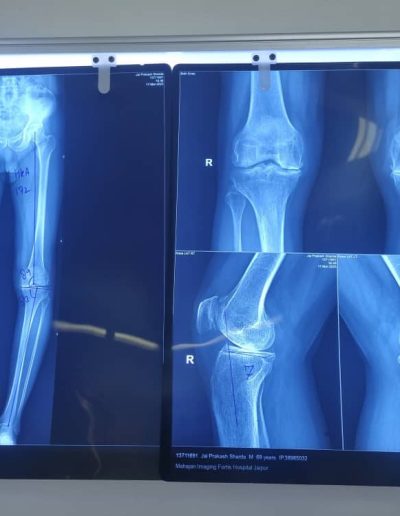

High tibial osteotomy and proximal fibula osteotomies are among the joint preservation surgery techniques that help to unload the arthritic joints, slow down inflammation and help in joint realignment, hopefully negating the need of knee replacement later.